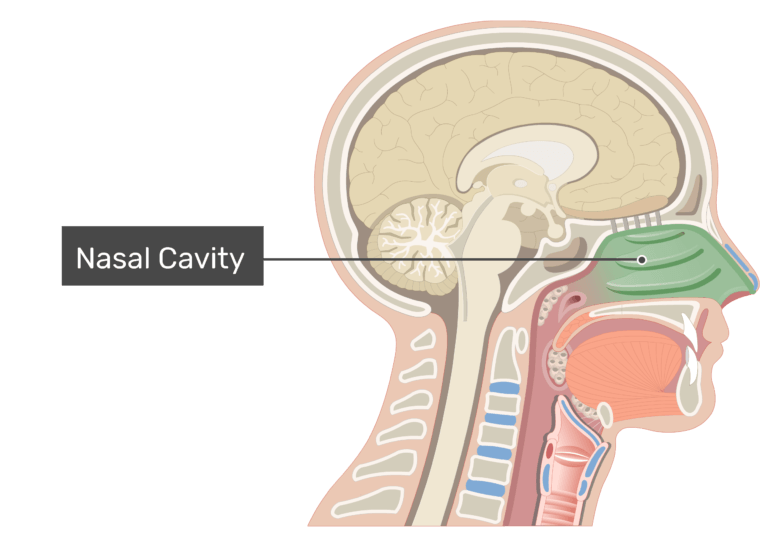

Projecting out of the lateral walls of the nasal cavity are curved shelves of bone. The flow of air from outside of the body to the lungs begins with the nose which is divided into the left and right nasal passages.

During inhalation air enters through the nostrils and passes via the nasal cavity into the pharynx and larynx the next sections in the respiratory tract to eventually reach the lungs. Anatomy and physiology of the nasal cavity inner nose and mucosa introduction. Anatomy of the nose.

The external nose consists of paired nasal bones and upper and lower lateral cartilages. The nasal cavity refers to the interior of the nose. The nasal cavity is the most superior part of the respiratory tract.